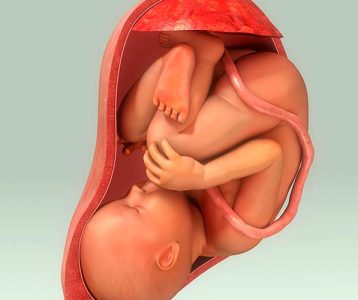

Para o presidente do Comitê Científico do Yakult International Symposia on Beneficial Microbes – Fundamental Science and Innovative Applications, Prof. Dr. Svetoslav Dimitrov Todorov, a ciência dos probióticos, assim como a compreensão do papel e da utilização desses microrganismos, vem sendo amadurecida. “Probióticos passaram de ‘simples’ produtos fermentados que melhoram o estado imunológico ou desequilíbrios gastrointestinais para ‘sofisticadas’ formulações farmacêuticas sob medida para otimizar várias funções fisiológicas”, ressalta.

De acordo com o professor, que é docente e pesquisador do Departamento de Alimentos e Nutrição Experimental da Faculdade de Ciências Farmacêuticas da Universidade de São Paulo, cabe aos cientistas reconhecerem que ainda estão na fase nascente da ciência dos probióticos, apesar de quase um século de exploração em suas aplicações. “Entretanto, hoje estamos mais perto de realizar o sonho de Hipócrates de que um dia nosso alimento se tornará Medicina e nossa Medicina se tornará alimento”, acrescenta.

- Probióticos e metabolismo do hospedeiro

- Probióticos e saúde intestinal

- Probióticos e resposta imune do hospedeiro